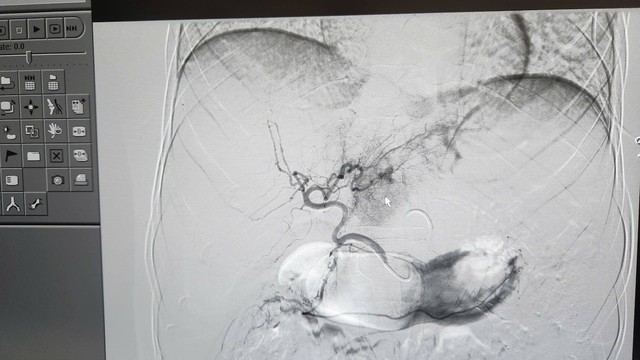

Hình ảnh lá gan bị vỡ của bệnh nhân. Ảnh: BVCC.

Kết quả chụp CT cho thấy bệnh nhân bị vỡ gan độ 4, ổ chảy máu đang hoạt động mạnh. Đây là tình trạng nguy kịch, nguy cơ tử vong rất cao nếu không được xử trí kịp thời.

Ca can thiệp do ê-kíp can thiệp mạch của Khoa Chẩn đoán hình ảnh thực hiện với sự chỉ đạo trực tiếp của bác sĩ CKII Ngô Vĩnh Hoài, Phó Trưởng khoa. Nhờ hệ thống chụp mạch số hóa xóa nền (DSA), các bác sĩ đã xác định chính xác vị trí tổn thương và kiểm soát hoàn toàn điểm chảy máu.

Theo bác sĩ Hoài, đây là kỹ thuật phức tạp, đòi hỏi thao tác chính xác từng milimet nhằm kiểm soát hoàn toàn điểm chảy máu. Phương pháp này giúp cầm máu tức thì, bảo tồn tối đa phần gan lành, đồng thời rút ngắn thời gian hồi phục và hạn chế biến chứng so với phẫu thuật thông thường.